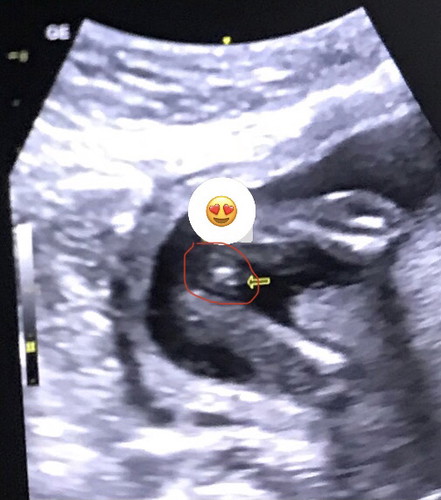

Not yet sure if boy or girl at 18 weeks

Hi mga Mii! Currently 18 weeks today, tinry lang i-check yung gender via ultrasound pero hindi pa talaga malinaw kaya hindi pa masabi ni Doc hehe. May same po ba dito ng picture sa scan mga mi if girl or boy.? Thank you